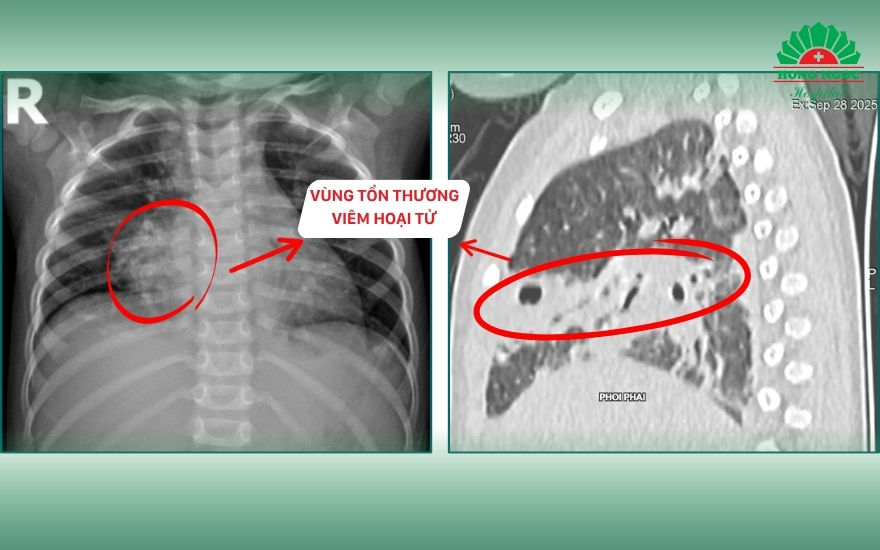

Kết quả chụp CT lồng ngực cho thấy tổn thương nghiêm trọng tại phổi phải với hình ảnh viêm phổi hoại tử, kích thước ổ tổn thương 40 x 42 x 20 mm, chiếm khoảng 1/4 thể tích phổi phải. Trẻ đồng thời có tràn dịch màng phổi hai bên dày khoảng 11 mm và xẹp hoàn toàn hai thùy dưới của phổi. Kết quả nội soi tai mũi họng ghi nhận viêm tai giữa ứ mủ hai bên. Các xét nghiệm vi sinh cho thấy test nhanh RSV dương tính, cấy dịch tỵ hầu phát hiện phế cầu, và PCR dịch tỵ hầu dương tính với HI, phế cầu và Mycoplasma IgM.

Kết quả CT và siêu âm ngực cho thấy bé N.P bị hoại tử phổi phải kích thước 40×42×20 mm kèm tràn dịch màng phổi hai bên, dày 11 mm.